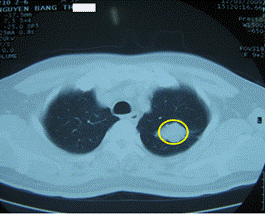

Hình 2: Hình ảnh chụp cắt lớp vi tính (CT) lồng ngực: có khối u phổi trái (trong vòng tròn màu vàng)

Kết quả giải phẫu bệnh: ung thư biểu mô tuyến.